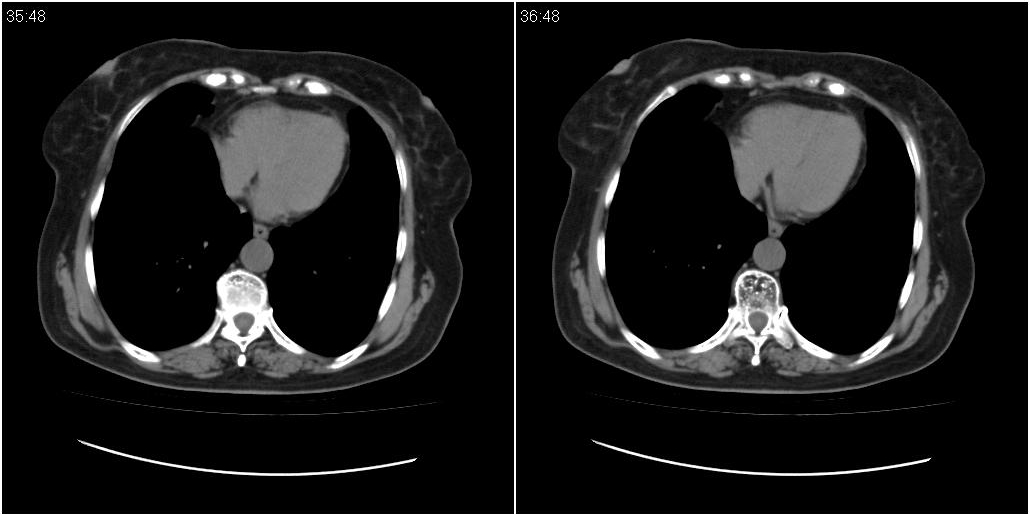

女性,72岁。去年9月份发现肺部病变,诊为肺结核并进行正规治疗至今,但复查后发现ct表现几乎没有变化。

双肺继发性肺结核并右肺中叶节段性肺不张,左下胸膜肥厚粘连。

双肺继发性肺结核并右肺中叶节段性肺不张

双肺继发型tb并右中叶内膜tb,轻度支扩,左下胸膜肥厚粘连。